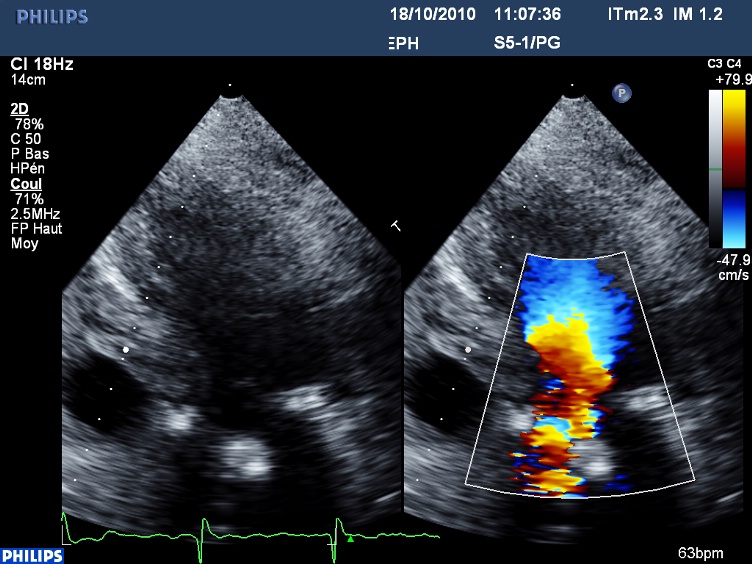

Pourtant il ne s’agit ni d’une thrombose de bioprothèse (au demeurant très rare en position aortique), ni d’une disproportion patient prothèse, mais d’un SAM (systolic anterior motion) de la grande valve mitrale, qui se replie dans la chambre de chasse du VG, ce qui engendre un obstacle sous aortique (Cf photo Doppler couleur) et une insuffisance mitrale :